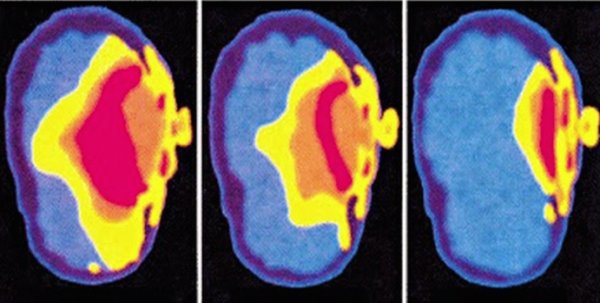

Bir grup bilim insanı, modern cihazların yaydığı elektromanyetik radyasyonun olası kanserojen etkileri hakkındaki endişelerini dile getirdi. Bilim insanları, özellikle kablosuz kulaklıklara dikkat çekerek, bu cihazların kulaktan beyne ciddi radyasyon ilettiğini belirttiler.

Bilim insanları, kablosuz iletişimde kullanılan elektrik ve radyo frekansı radyasyonuna (RFR) ve iyonlaştırıcı olmayan radyasyona maruz kalan kişilerin, taşıdığı riskler hakkında ciddi endişeler dile getirdiler. Bu da Bluetooth, Wi-Fi ve hücresel veri gibi teknolojilerin ne derece tehlikeli olabileceğini gözler önüne seriyor.